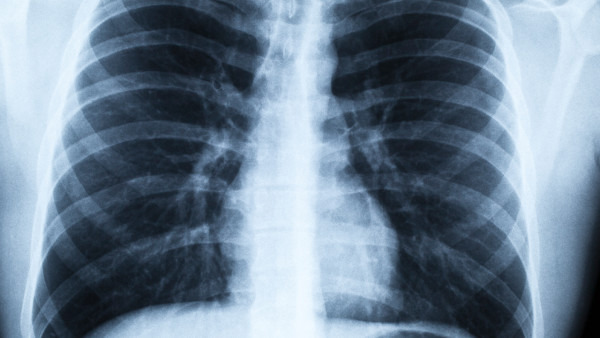

肺穿孔导致的脑气栓患者会同时伴有神经症状、肢体抽搐、习惯性昏睡甚至昏迷等症状。使用听诊器听诊的话,会出现痰湿音,X线检查会显示出明显的斑点以及片状阴影。同时会有明显的气胸、血胸的现象。临床急诊时,病人常会出现昏睡状态,言语极少,不愿意答话,呼吸极度困难,咯血,吐白沫痰等。